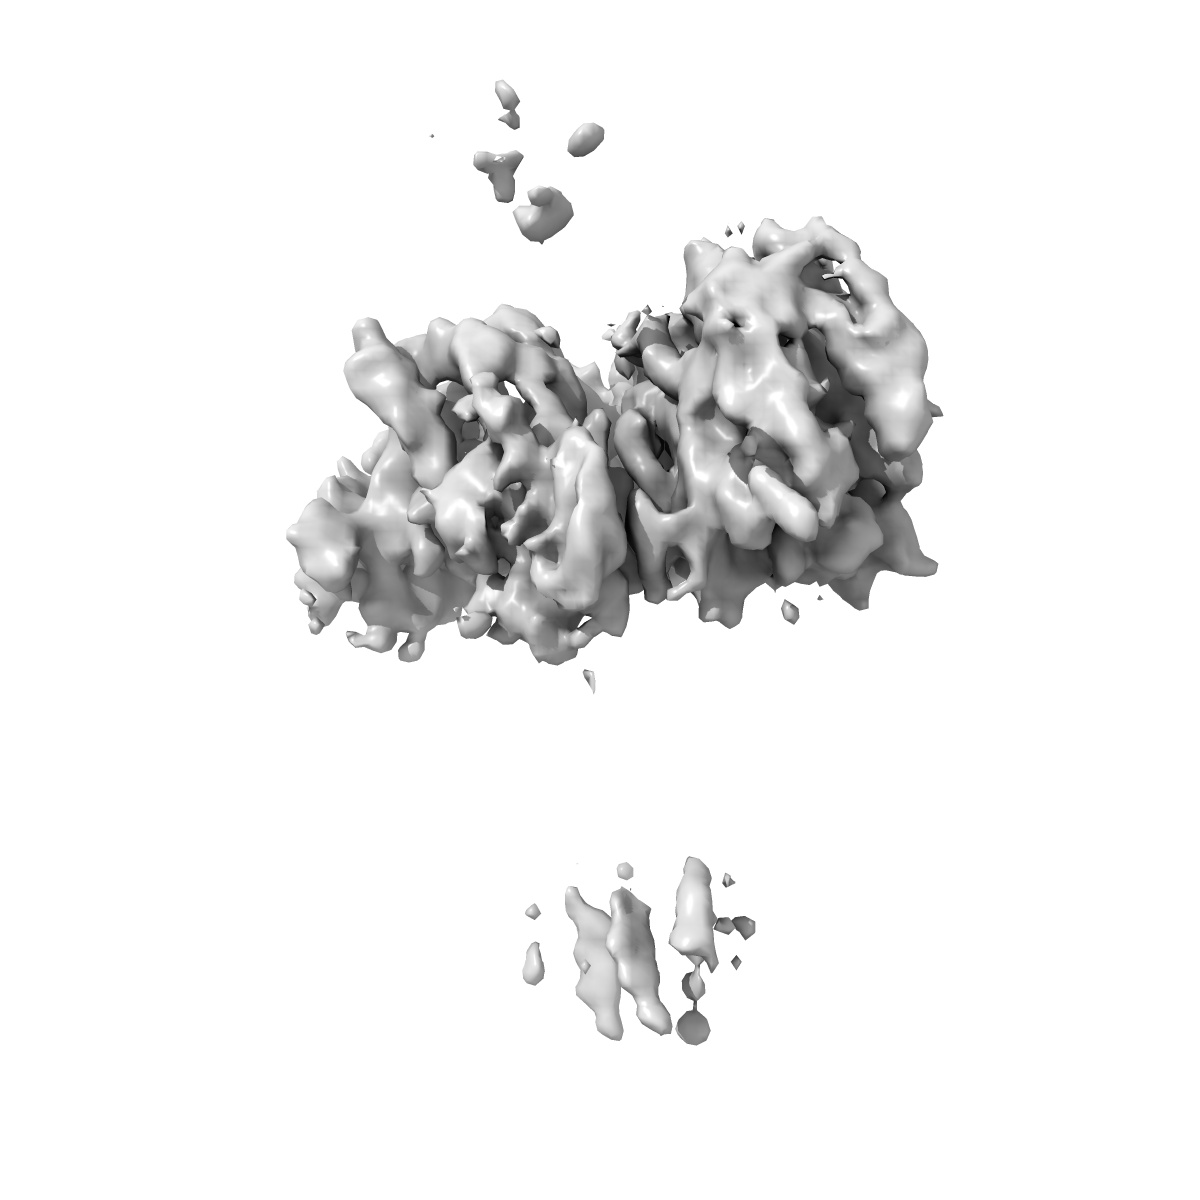

Rapid screening cryo-EM map of CAK bound to BS-181 (grid VC8-1, 1hr collection)

Single-particle3.7 Å

Sample: CDK-activating kinase

High-resolution cryo-EM of the human CDK-activating kinase for structure-based drug design.

(2024) Nat Commun , 15 , 2265 - 2265